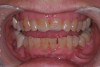

(11.) A patient presented with advanced generalized wear of her anterior teeth, and was displeased with their overall appearance because of their color and wear.

Figure 11

A patient presented with advanced generalized wear of her anterior teeth (Figure 10 and Figure 11). She was displeased with their overall appearance because of their color and wear (Figure 12). A complete examination was performed, revealing instability in her temporomandibular lateral poles bilaterally, sore muscles of mastication, advanced wear, a CR/MIP discrepancy, and loss of her anterior guidance due to the wear. Although the topic is beyond the scope of this article, the patient was also screened for possible sleep apnea. This included an evaluation of the Mallampati score, previous sleep therapy evaluation or treatment, snoring history, an evaluation of her neck size, her weight status, and the presence of the tonsils and their size. In every case, if this clinician suspects airway obstruction to be playing a role in tooth wear issues, the patient is referred to a sleep physician. The patient in this case displayed few apnea risk factors, and the patient’s anterior wear facets fit together like a “lock and key” pattern seen in parafunctional activity. Splint therapy was initiated to stabilize the joints and muscles. A repeatable CR position was verified through load testing. At this point diagnostic models, photographs, a CR bite record, and a facebow were taken and recorded.